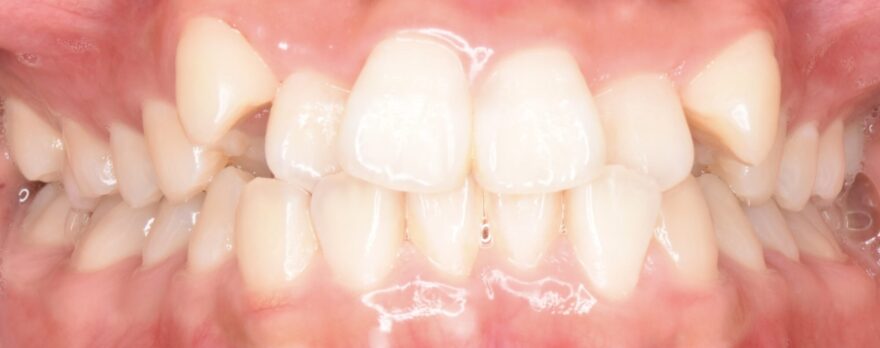

初診時の口腔内写真

上の八重歯が気になります。

八重歯の内側への移動量がとても多いことがわかります。